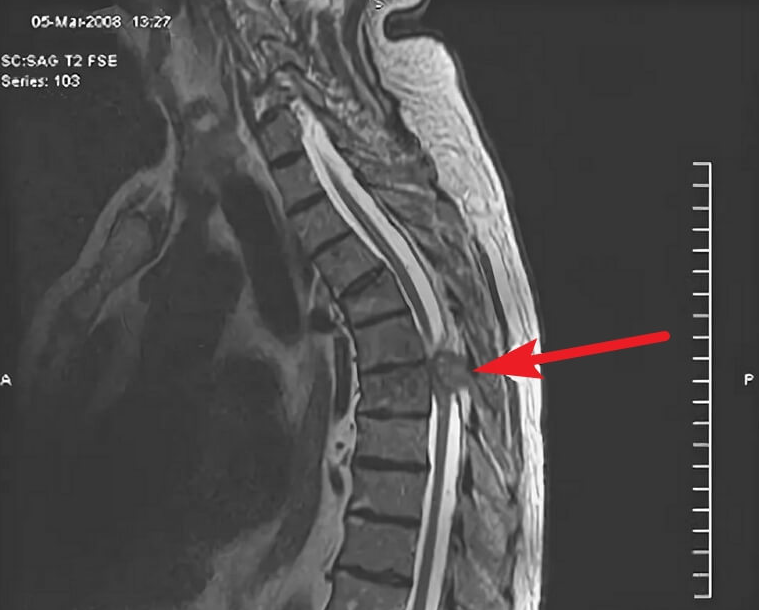

- Магнитно-резонансная томография. В основе метода — точная визуализация благодаря созданию магнитного поля и радиоволн. МРТ — предпочтительный метод диагностики новообразований спинного мозга и окружающих тканей. Для детального исследования конкретной области и структур возможно введение контрастных веществ.